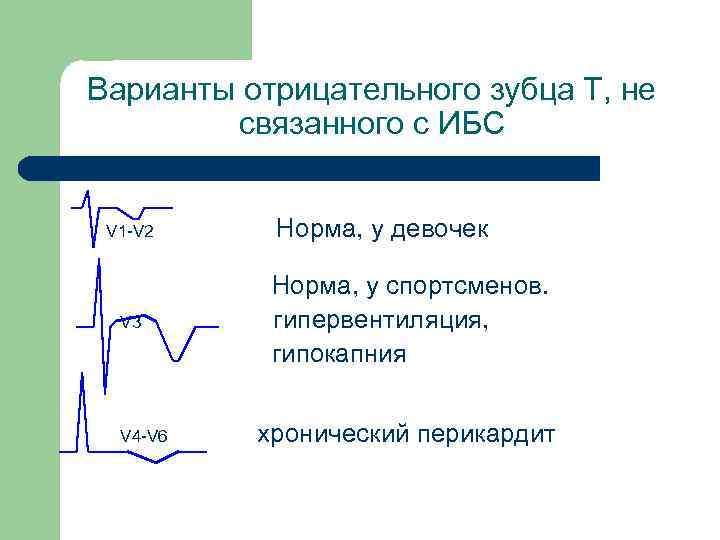

Инверсия зубца Т «Болезней много, а зубец Т один» Л. И. Фогельсон

Варианты отрицательного зубца Т, не связанного с ИБС V 1 -V 2 V 3 V 4 -V 6 Норма, у девочек Норма, у спортсменов. гипервентиляция, гипокапния хронический перикардит